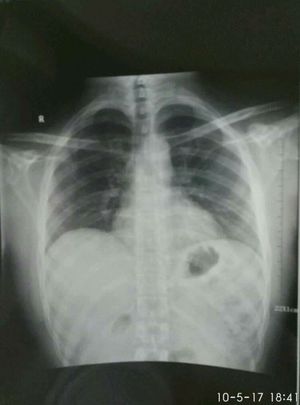

Is this cxr normal ?

Yes